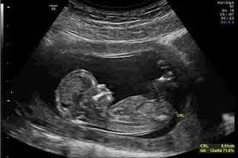

Masa 20w saya scan KK, mula2 dia terlentang. Lepastu cepat2 dia bersujud. Nakaaaaalll!!! Tak dapat tengok gender. So saya booking details scan & 5D merdeka nanti 25w. Harap dia bagi chance la dkt ibu dia nie HAHAHA

scan msa check up 22week x nmpk lg jantina sbb baby kepit😂😂

saya 23 minggu baby beri kerjasama dah tunjuk gender dya